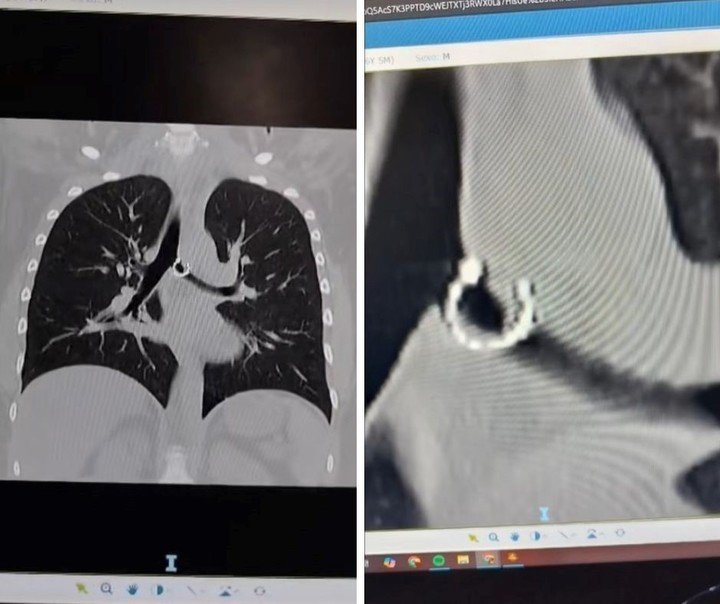

A través de este posteo, visto por más de cuatro millones de personas, aseguró haber aspirado un aro que llevaba en su nariz sin darse cuenta —lo hizo mientras dormía—, lo que le causó problemas de salud. Además, mostró radiografías e imágenes de la pieza de joyería.

«Ahorita me río, pero en el momento fue un horror. Los médicos estaban impactados, así como yo y todos a mi alrededor», escribió el 7 de diciembre la joven, quien, de acuerdo con el portal de noticias Need To Know, tiene 26 años y es de México.